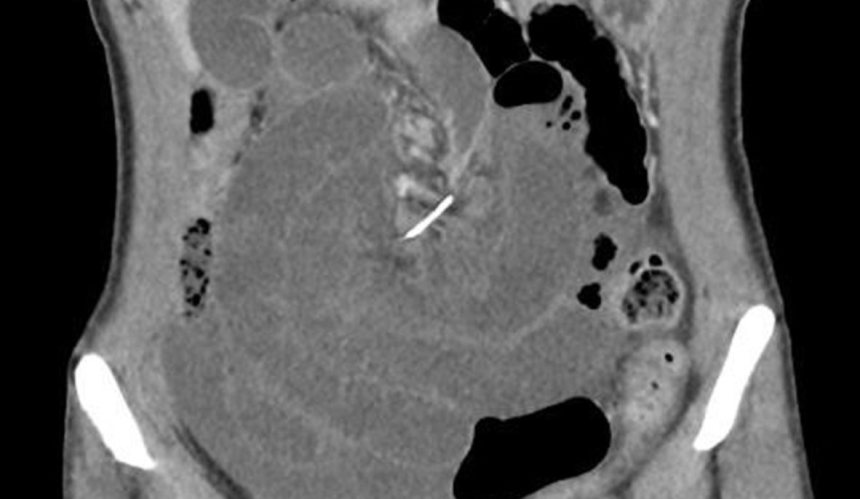

Všetko odhalila až CT snímka čriev, kde našli kus tenkého drôtu z kovu. Najzaujímavejším na celom prípade je však čas, ktorý tam objavený predmet strávil. Zubný strojček totiž naposledy používala zhruba pred 10 rokmi, čiže keď mala 20 rokov, píšu v odbornom článku na BMJ Case Reports.